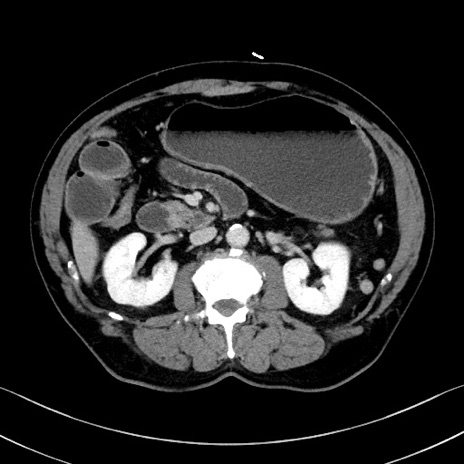

症例35(横断像)

冠状断像

【症例】70歳代 男性

【主訴】腹部膨満、嘔吐

【現病歴】昨日より腹部膨満感出現。本日増悪し、仙痛出現。嘔吐あり、受診。

【既往歴】糖尿病、胆摘後

【身体所見】BP 149/80mmHg、HR 74/min、BT 35.9℃、腹部:膨満、軟、圧痛なし。腸雑音減弱あり。上腹部正中切開瘢痕あり。

【データ】WBC 13500、CRP 1.72